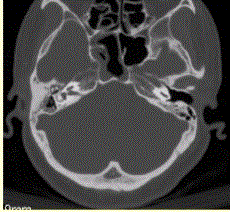

问题 患者男,20岁,外伤后右耳听力下降伴面瘫7d。临床检查,右耳传导性耳聋,发现脑脊液耳瘘。CT表现如下图。 对于颞骨骨折,最佳的影像学检查方法是

选项 A.X线平片 B.常规CT C.MRI D.HRCT E.CT增强检查

答案 D